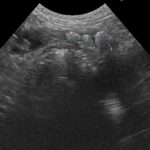

かかりつけ医で定期的に超音波検査で腎結石のモニターをしていたところ、急に腎盂が拡張してきたので早急に対応して欲しいと連絡がありました。尿管結石により尿路閉塞が起こっていました。マイクロサージェリーで尿管を2箇所切開し、尿管結石を摘除しました。術後の狭窄予防に一時的に尿管ステントを留置しています。術後翌日から、腎盂拡張は解消しましたが、術後の経過により、生体にとって異物となる尿管ステントは抜去する予定です。